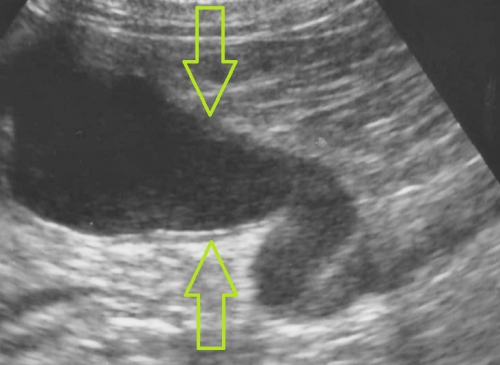

レントゲン検査により腎臓や尿管に結石が見つかった場合、さらに超音波検査によって結石の正確な位置関係とそれが周囲に及ぼす影響を評価します。下の2枚の写真は超音波検査の画像です。尿は左から右写真方向に「黒い管」として見える腎盂~尿管の中を流れます。

右下写真の黄色い円の中に見える「白いカタマリ」が尿管結石で、おおよそ3ミリくらいの直径があり、尿管を閉塞しています。

腎臓でつくられた尿がつまっているために尿管は重度に拡張しており、結石のすぐ上流で直径が4mm(赤矢印)、さらに腎臓の出口付近では1cm以上(緑矢印)にもなっており、腎臓内が拡張した水腎症になってしまっています。

通常では猫の尿管は極めて細いため超音波検査ではほぼ見ることができませんので閉塞の程度をイメージできるのではと思います。